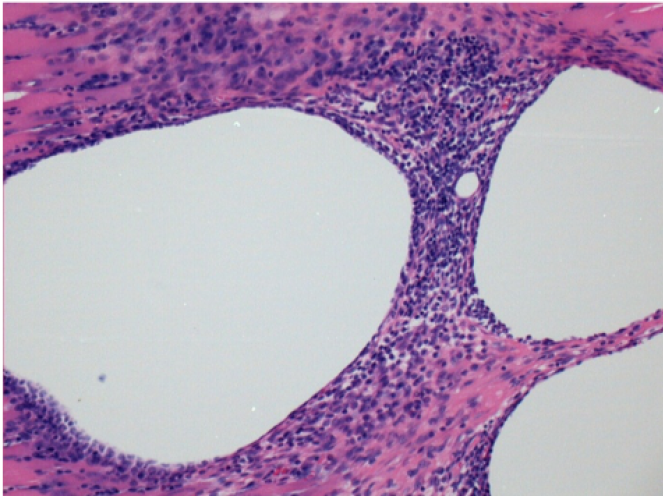

Here you may see the formation of the vacuoles which are surrounded by lymphocytes. Vacuoles are different from tissue necrosis . The presence of lymphocytes is related to the permeability of the cell membranes.

What is seen in black on the pictures is not a necrosis like could imagine some scientifics !

In fact, 4 conclusions have to be taken in consideration